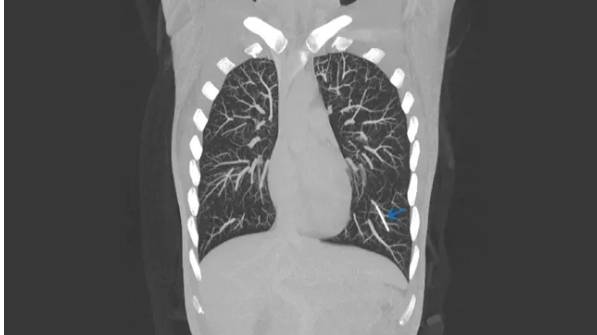

![팔뚝에 삽입된 피임 임플란트가 핏줄을 타고 폐에 박혔다. CT 영상에서 왼쪽 폐 아래 파란색 화살표가 가리키고 있는 흰색 선이 피임 임플란트다. [BMJ Case Reports 캡쳐]](https://img1.daumcdn.net/thumb/R658x0.q70/?fname=https://t1.daumcdn.net/news/202507/02/KorMedi/20250702121125892yogq.jpg)

의사는 영상 검사를 한 결과 이 임플란트가 제자리에 삽입돼 있지 않다는 걸 알았다. 임플란트는 삽입 1주일 뒤 이동하기 시작해 위 팔의 정맥으로 이동했다. 이어 심장으로 향해 우심방과 심실을 통과하고 좌측 폐동맥을 통해 폐에 박혔다.